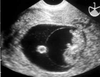

pseudosac

(ectopic pregnancy)